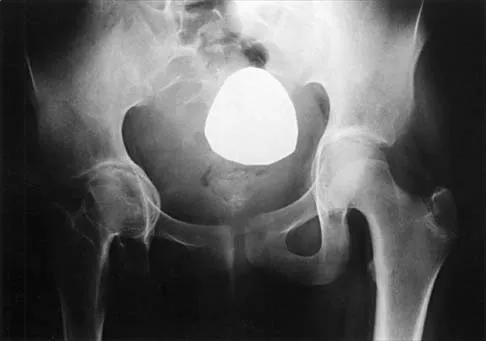

Figure 44 shows the radiograph of an 11-year-old girl who has hip pain. Further diagnostic workup should include

Explanation

The patient has severe acetabular protrusio, a condition that is frequently associated with Marfan syndrome. An echocardiogram is necessary to rule out the most serious consequence of this syndrome, aortic root widening, which can lead to aortic valve dysfunction or fatal aortic rupture. An electromyogram may be indicated for Charcot-Marie-Tooth disease, which is associated with acetabular dysplasia, but not protrusio. The renal ultrasound, the MRI scan, and the biopsy would be of no value in this patient. Protrusio can also be seen in patients with osteogenesis imperfecta and juvenile rheumatoid arthritis. Steel HH: Protrusio acetabuli: Its occurrence in the completely expressed Marfan syndrome and its musculoskeletal component and a procedure to arrest the course of protrusion in the growing pelvis. J Pediatr Orthop 1996;16:704-718.

- Wenger DR, Ditkoff TJ, Herring JA, Mauldin DM: Protrusio acetabuli in Marfan's syndrome. Clin Orthop 1980;147:134-138.